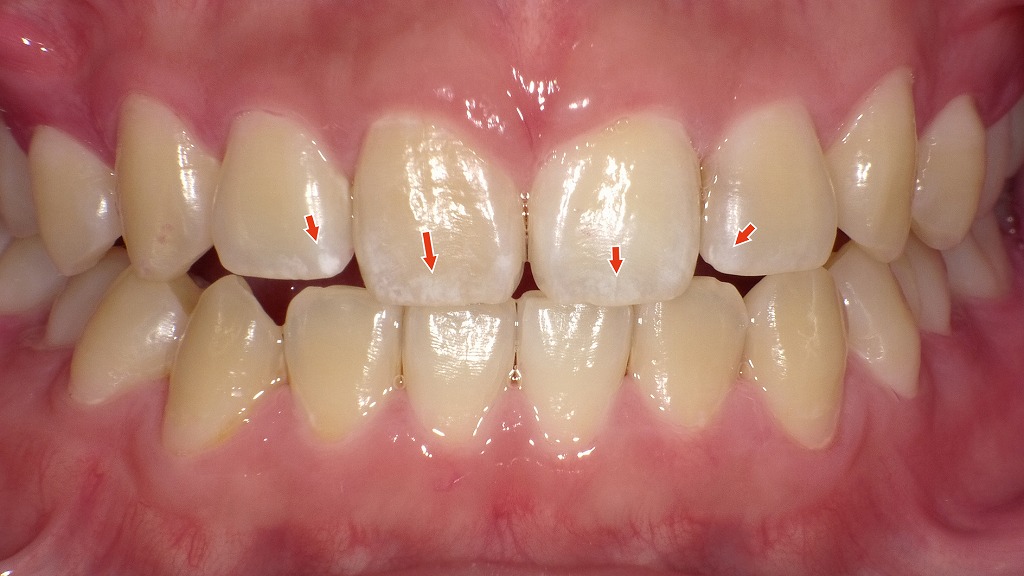

2枚目の画像:ホワイトニング後

2枚目の画像では、ホワイトニング後の状態を示しています。歯全体が明るくトーンアップしており、周囲の色とのコントラストが減少したことで、ホワイトスポットがほとんど目立たなくなっています。ホワイトニングによって歯全体の明度が上がることで、白斑が自然に馴染み、全体として均一な印象に改善されています。

このように、ホワイトスポット自体を「消す」ことはできませんが、ホワイトニングで目立たなくすることは可能です。